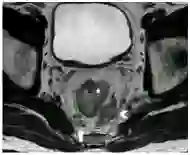

T2加权像粘液性肿瘤呈明显高密度信号,外周蕾丝样增强。MRI检查缺点如下:粘液性肿瘤弥漫性浸润生长已传播至肠壁外,而肠壁解剖结构仍完整;放化疗后即便已无肿瘤、唯留粘液湖时,粘液性肿瘤仍倾向于保持高密度信号(图8);粘液性肿瘤T2加权像呈水样高密度信号,而周围盆腔脂肪也是高密度信号,因此薄层高分辨非压脂轴位T2加权像很易漏诊,此时需调整MRI参数,采用T2加权压脂像抑制脂肪信号,或非压脂轴位T2加权像采用二种不同高回波时间(TE)检测肿瘤,因为周围盆腔脂肪产生二种不同的密度信号(图9)。

图8  65岁女性直肠粘液腺癌放化疗后,轴位T2加权像显示直肠壁粘液池高密度信号(长箭头)和直肠系膜淋巴结(箭头),较前无显著变化,临床定义为无治疗反应,但术后病理证实为粘液池,未见肿瘤细胞。